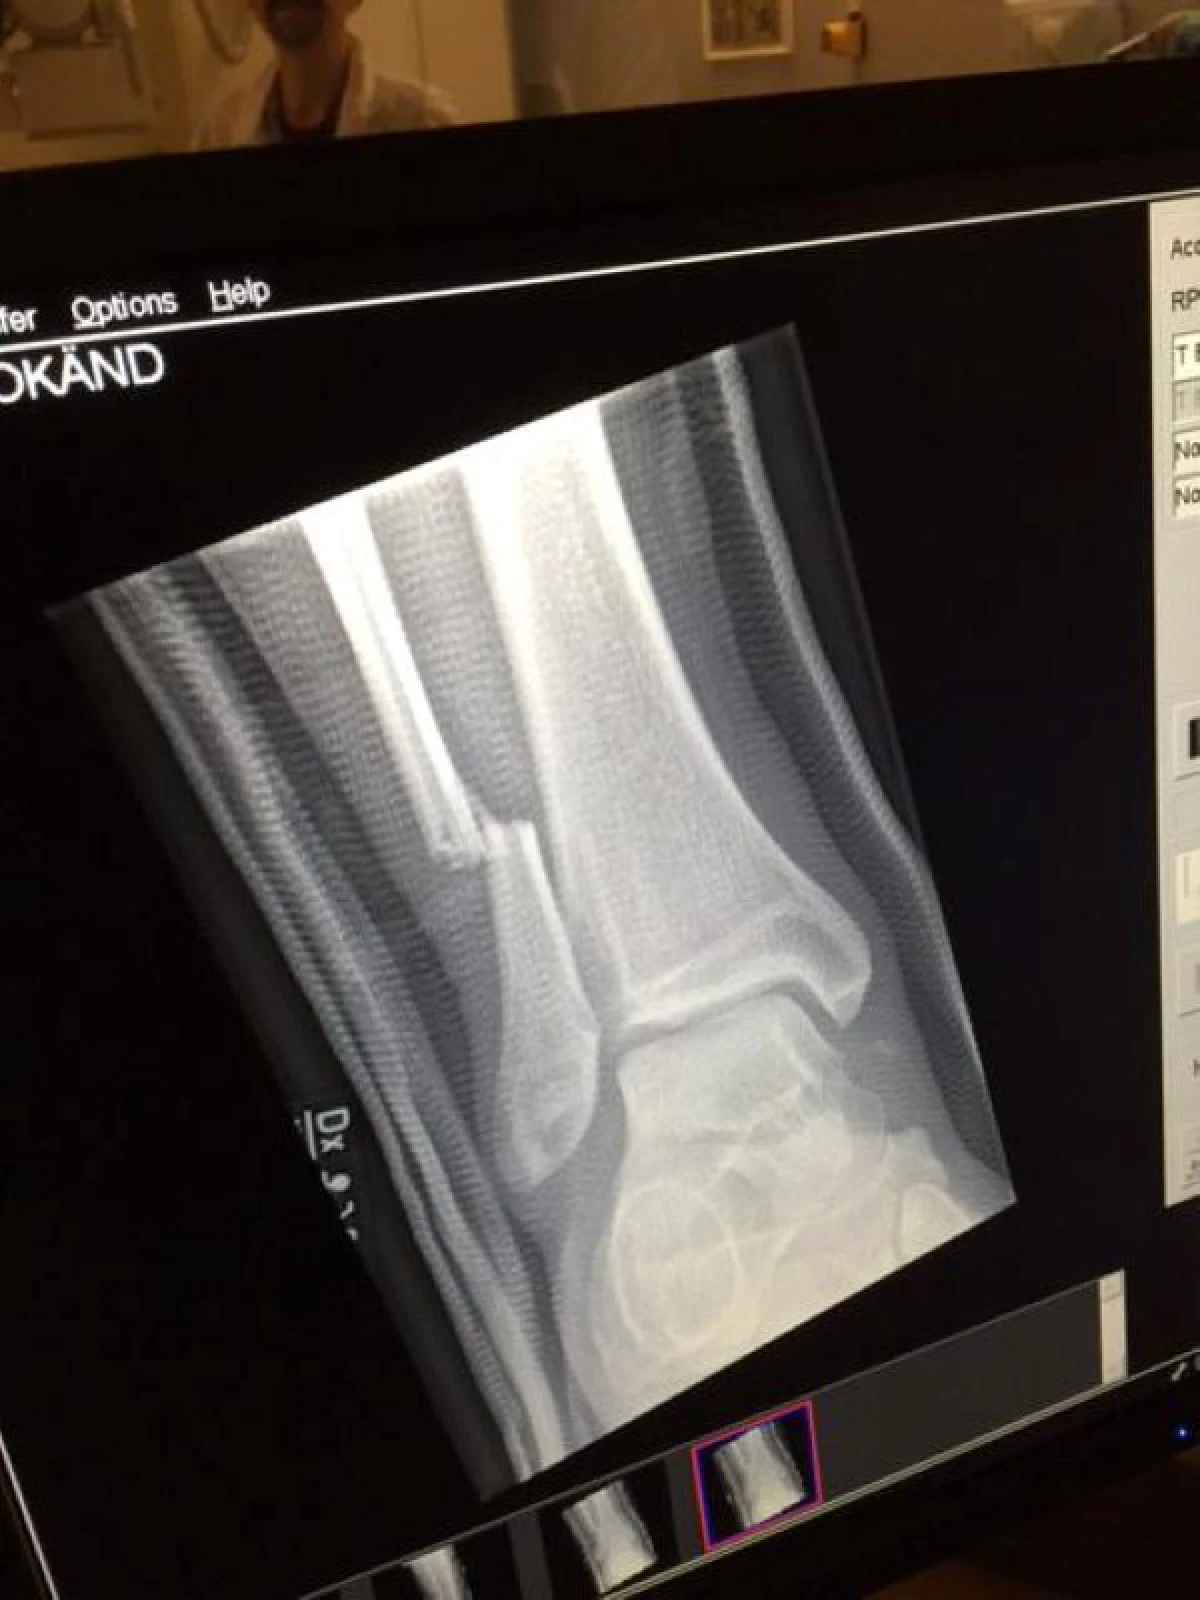

ไม่กี่ชั่วโมงต่อมา เฟซบุ๊ก Foo Fighter ได้เผยแพร่ภาพเอกซเรย์กระดูกขาของนายเดฟและพบว่าขาของเขาหักจริงๆ